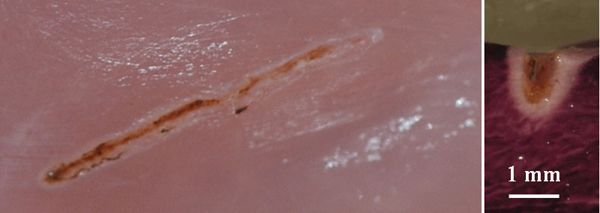

A core functionality of the TOP surgery system is the ability to precisely maintain constant temperature at the tip independent of the speed of the surgeon’s hand. This is made possible by a real-time temperature sensing and adjustment system. The temperature selected by the operator is maintained independent of the speed of movement through the tissue or the type and consistency of the tissue—a fundamental advancement in thermal cutting. This regulating mechanism dramatically reduces the effect of the movement speed as a variable. The cutting effect and the zone of thermal necrosis are constant for each temperature setting used, which significantly reduces the variability of depth of cut and collateral thermal damage due to changes in speed of movement. When necessary, this automatic power control delivers more power for fast cutting or cutting of fibrotic tissue, and minimizes power output for reduced cutting speeds to protect the patient. The TOP automatic power control (Figure 5) produces a deeper cut with minimal collateral thermal damage versus a cut performed with fixed power (Figure 6). Additionally, for safety the surgery system is capable of sensing a stop in hand movement and shuts down the power to avoid tissue overheating.

Fig 5. Laser cut using TOP system with automatic power control; cutting depth is 2.3 mm, and coagulation depth is 0.23 mm.

Figure 5

Fig 6. Laser cut using fixed power (3 W CW); cutting depth is 0.85 mm, and coagulation depth is 0.31 mm.

Figure 6